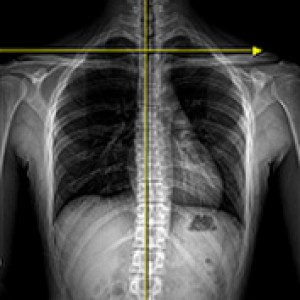

성인의 80%~90%에서 골반 부정렬이 발견되었으며,

그 중 3분의 1은 무증상, 3분의 2는 요통, 골반통 등의 증상을 호소한다.

Wolf Schamberger - The Malalignment Syndrome 中

골반 교정 왜 중요할까요?

골반은 허리와 다리를 연결하는 상하체 균형의 핵심 역할을 합니다.